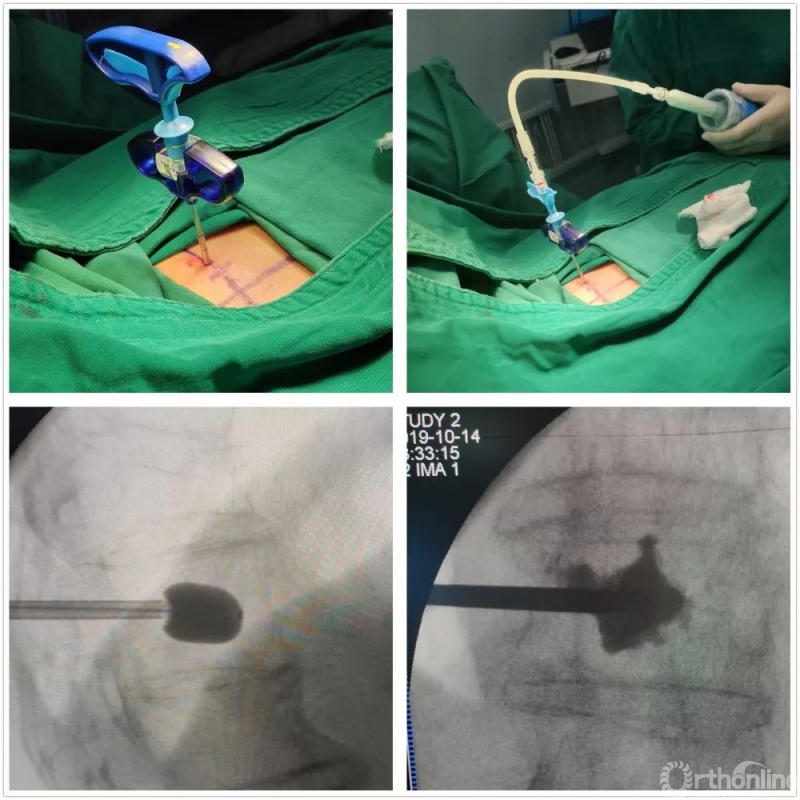

经皮椎体成形术

在天津医院脊柱四科的学习中,我第一次接触到了显微镜在脊柱外科手术中的应用,通过作为助手同台协助徐宝山教授手术,我有机会在显微镜的目镜下观察徐主任进行颈椎前路减压融合,在摘除部分髄核,适度地撑开椎间隙后,将显微镜引入辅助操作,刮匙清理残余的椎间盘,刮除上下软骨终板,切除后纵韧带,利用磨钻磨除部分增生钩椎关节及椎体后缘全部增生骨赘,显露神经根及硬膜囊,上下两侧充分扩大神经根管……整个操作流程非常清晰、流畅。

显微镜辅助下颈椎前路ACDF术

我深深地体会到了在显微镜辅助下行颈前路手术的安全与便捷:显微镜下光线好、图像三维立体,放大倍数可于4-20倍范围内自由调节,术中可清晰辨认椎体后缘、后纵韧带、硬膜及微小血管等结构,从而可以更精确的对椎体后缘骨赘、神经根管口、后纵韧带进行彻底减压,极大提高了治疗效果,减少了脊髓、血管、神经损伤等并发症发生可能,据统计显微镜下手术神经组织受损的发生率仅为0.1%,明显低于常规开放手术。